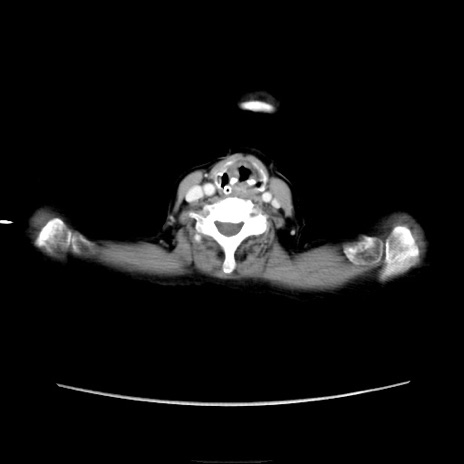

症例40(横断像)

【症例】90歳代女性

【主訴】腹痛・嘔吐

【現病歴】 食欲低下、嘔吐があり昨日他院受診。肺炎と診断され入院となる。入院後より腹部全体に圧痛あり。胃管留置され経過みていたが、症状持続するため、

当院転院となる。

【既往歴】胸椎圧迫骨折、胆石症

【身体所見】腹部:中央に激痛あり、圧痛あり、反跳痛不明

【データ】WBC 17100、CRP 18.82

横断像